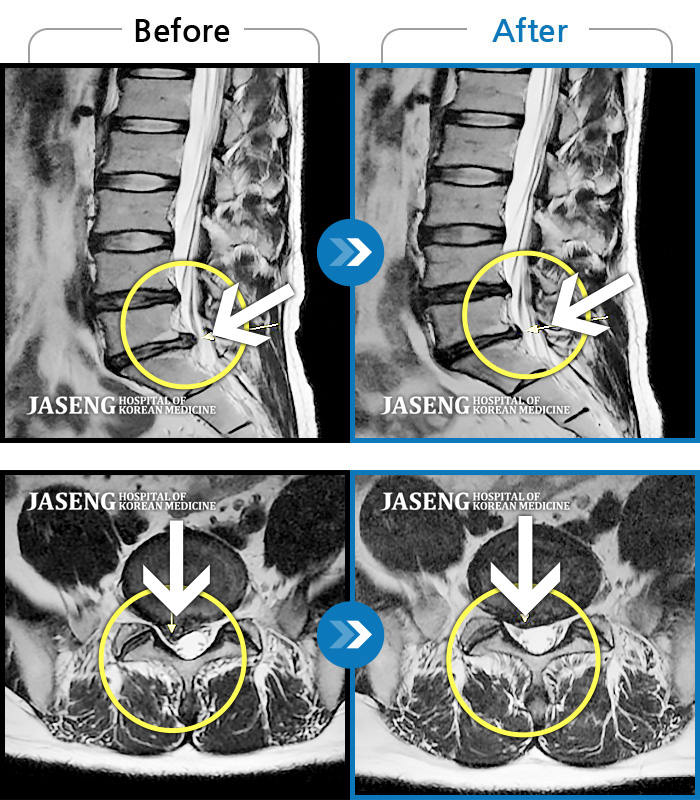

허리디스크

울산 · 정운석 원장

우측 하요추부 통증-우측 둔부-소퇴 후면 통증/비증

촬영시기

2021.08.08 ~ 2021.08.13

2021.08.20